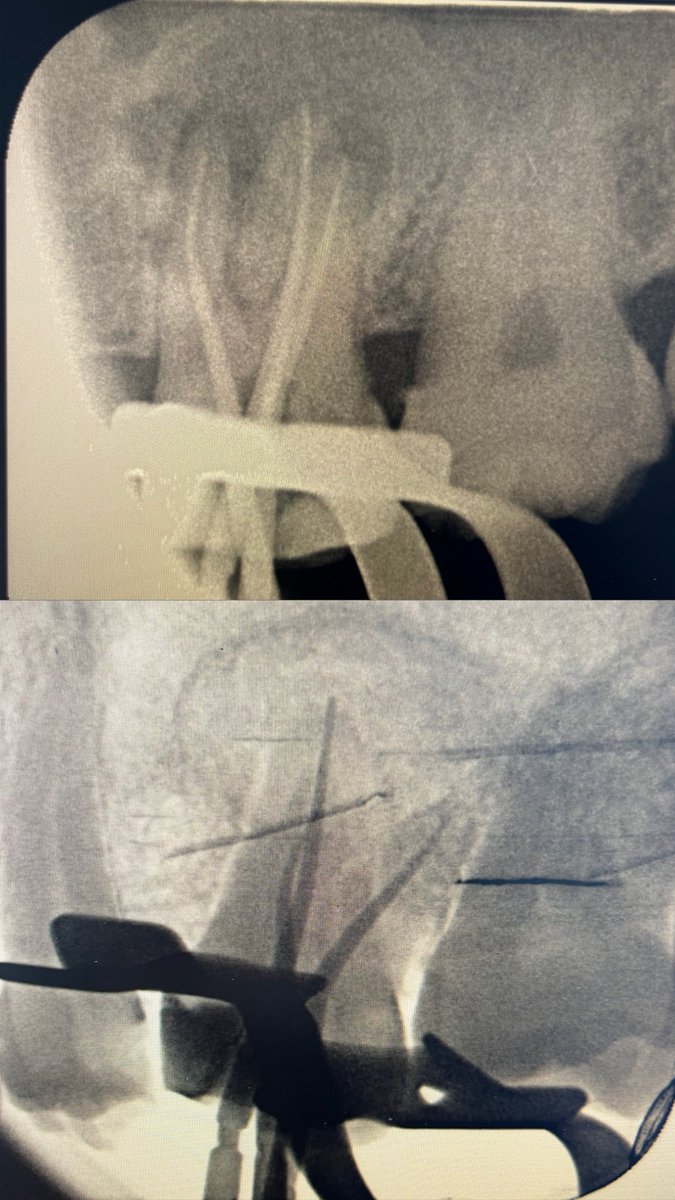

حالة جديدة اليوم ❤️

Root Canal Treatment for #36

The patient complained of severe pain,after examination we decided to do RCT.

Dx: SIP,NAP

ML wall is replaced then started RCT.

Single Cone and BC Sealer are used